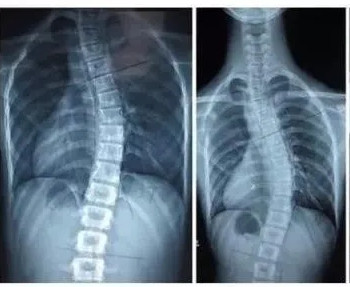

脊柱側(cè)彎是一種脊柱的三維畸形,在失狀面,冠狀面,橫斷面上的序列均會(huì)產(chǎn)生異常。在X光檢查中如果顯示脊柱有10度以上的側(cè)方彎曲,即會(huì)診斷為脊柱側(cè)彎。

脊柱側(cè)彎的X線檢查